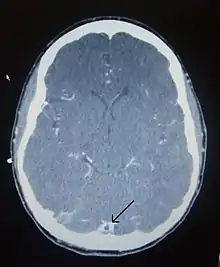

There are various neuroimaging investigations that may detect cerebral sinus thrombosis. Cerebral edema and venous infarction may be apparent on any modality, but for the detection of the thrombus itself, the most commonly used tests are computed tomography (CT) and magnetic resonance imaging (MRI), both using various types of radiocontrast to perform a venogram and visualise the veins around the brain.[2]

Computed tomography, with radiocontrast in the venous phase (CT venography or CTV), has a detection rate that in some regards exceeds that of MRI. The test involves injection into a vein (usually in the arm) of a radioopaque substance, and time is allowed for the bloodstream to carry it to the cerebral veins – at which point the scan is performed. It has a sensitivity of 75–100% (it detects 75–100% of all clots present), and a specificity of 81–100% (it would be incorrectly positive in 0–19%). In the first two weeks, the "empty delta sign" may be observed (in later stages, this sign may disappear).[6]